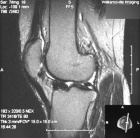

T.F. - 34 year old woman with a history of arthroscopic and open left knee surgeries in 2003 presenting with increased left knee pain and swelling

Zoom image: Radiological image Radiological image.